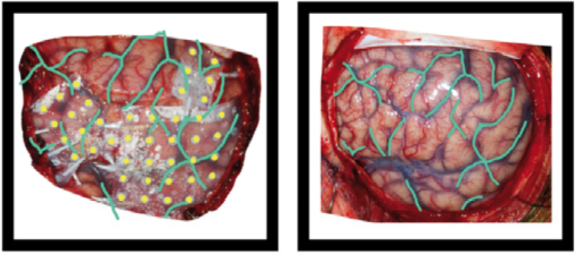

These can include photos of the electrodes on the brain surface, photos of anatomical features or landmarks (such as sulcal structure), and fiducials. Photos can also include an X-ray picture, a flatbed scan of a schematic drawing made during surgery, or screenshots of a brain rendering with electrode positions. The photos may need to be cropped and/or blurred to conceal identifying features or entirely omitted prior to sharing, depending on obtained consent.

Example of the operative photo of ECoG electrodes (here is an annotated example in which electrodes and vasculature are marked, taken from Hermes et al., JNeuroMeth 2010).

Below is an example of a volume rendering of the cortical surface with a superimposed subdural electrode implantation. This map is often provided by the EEG technician and provided to the epileptologists (for example, see Burneo JG et al. 2014. doi:10.1016/j.clineuro.2014.03.020).